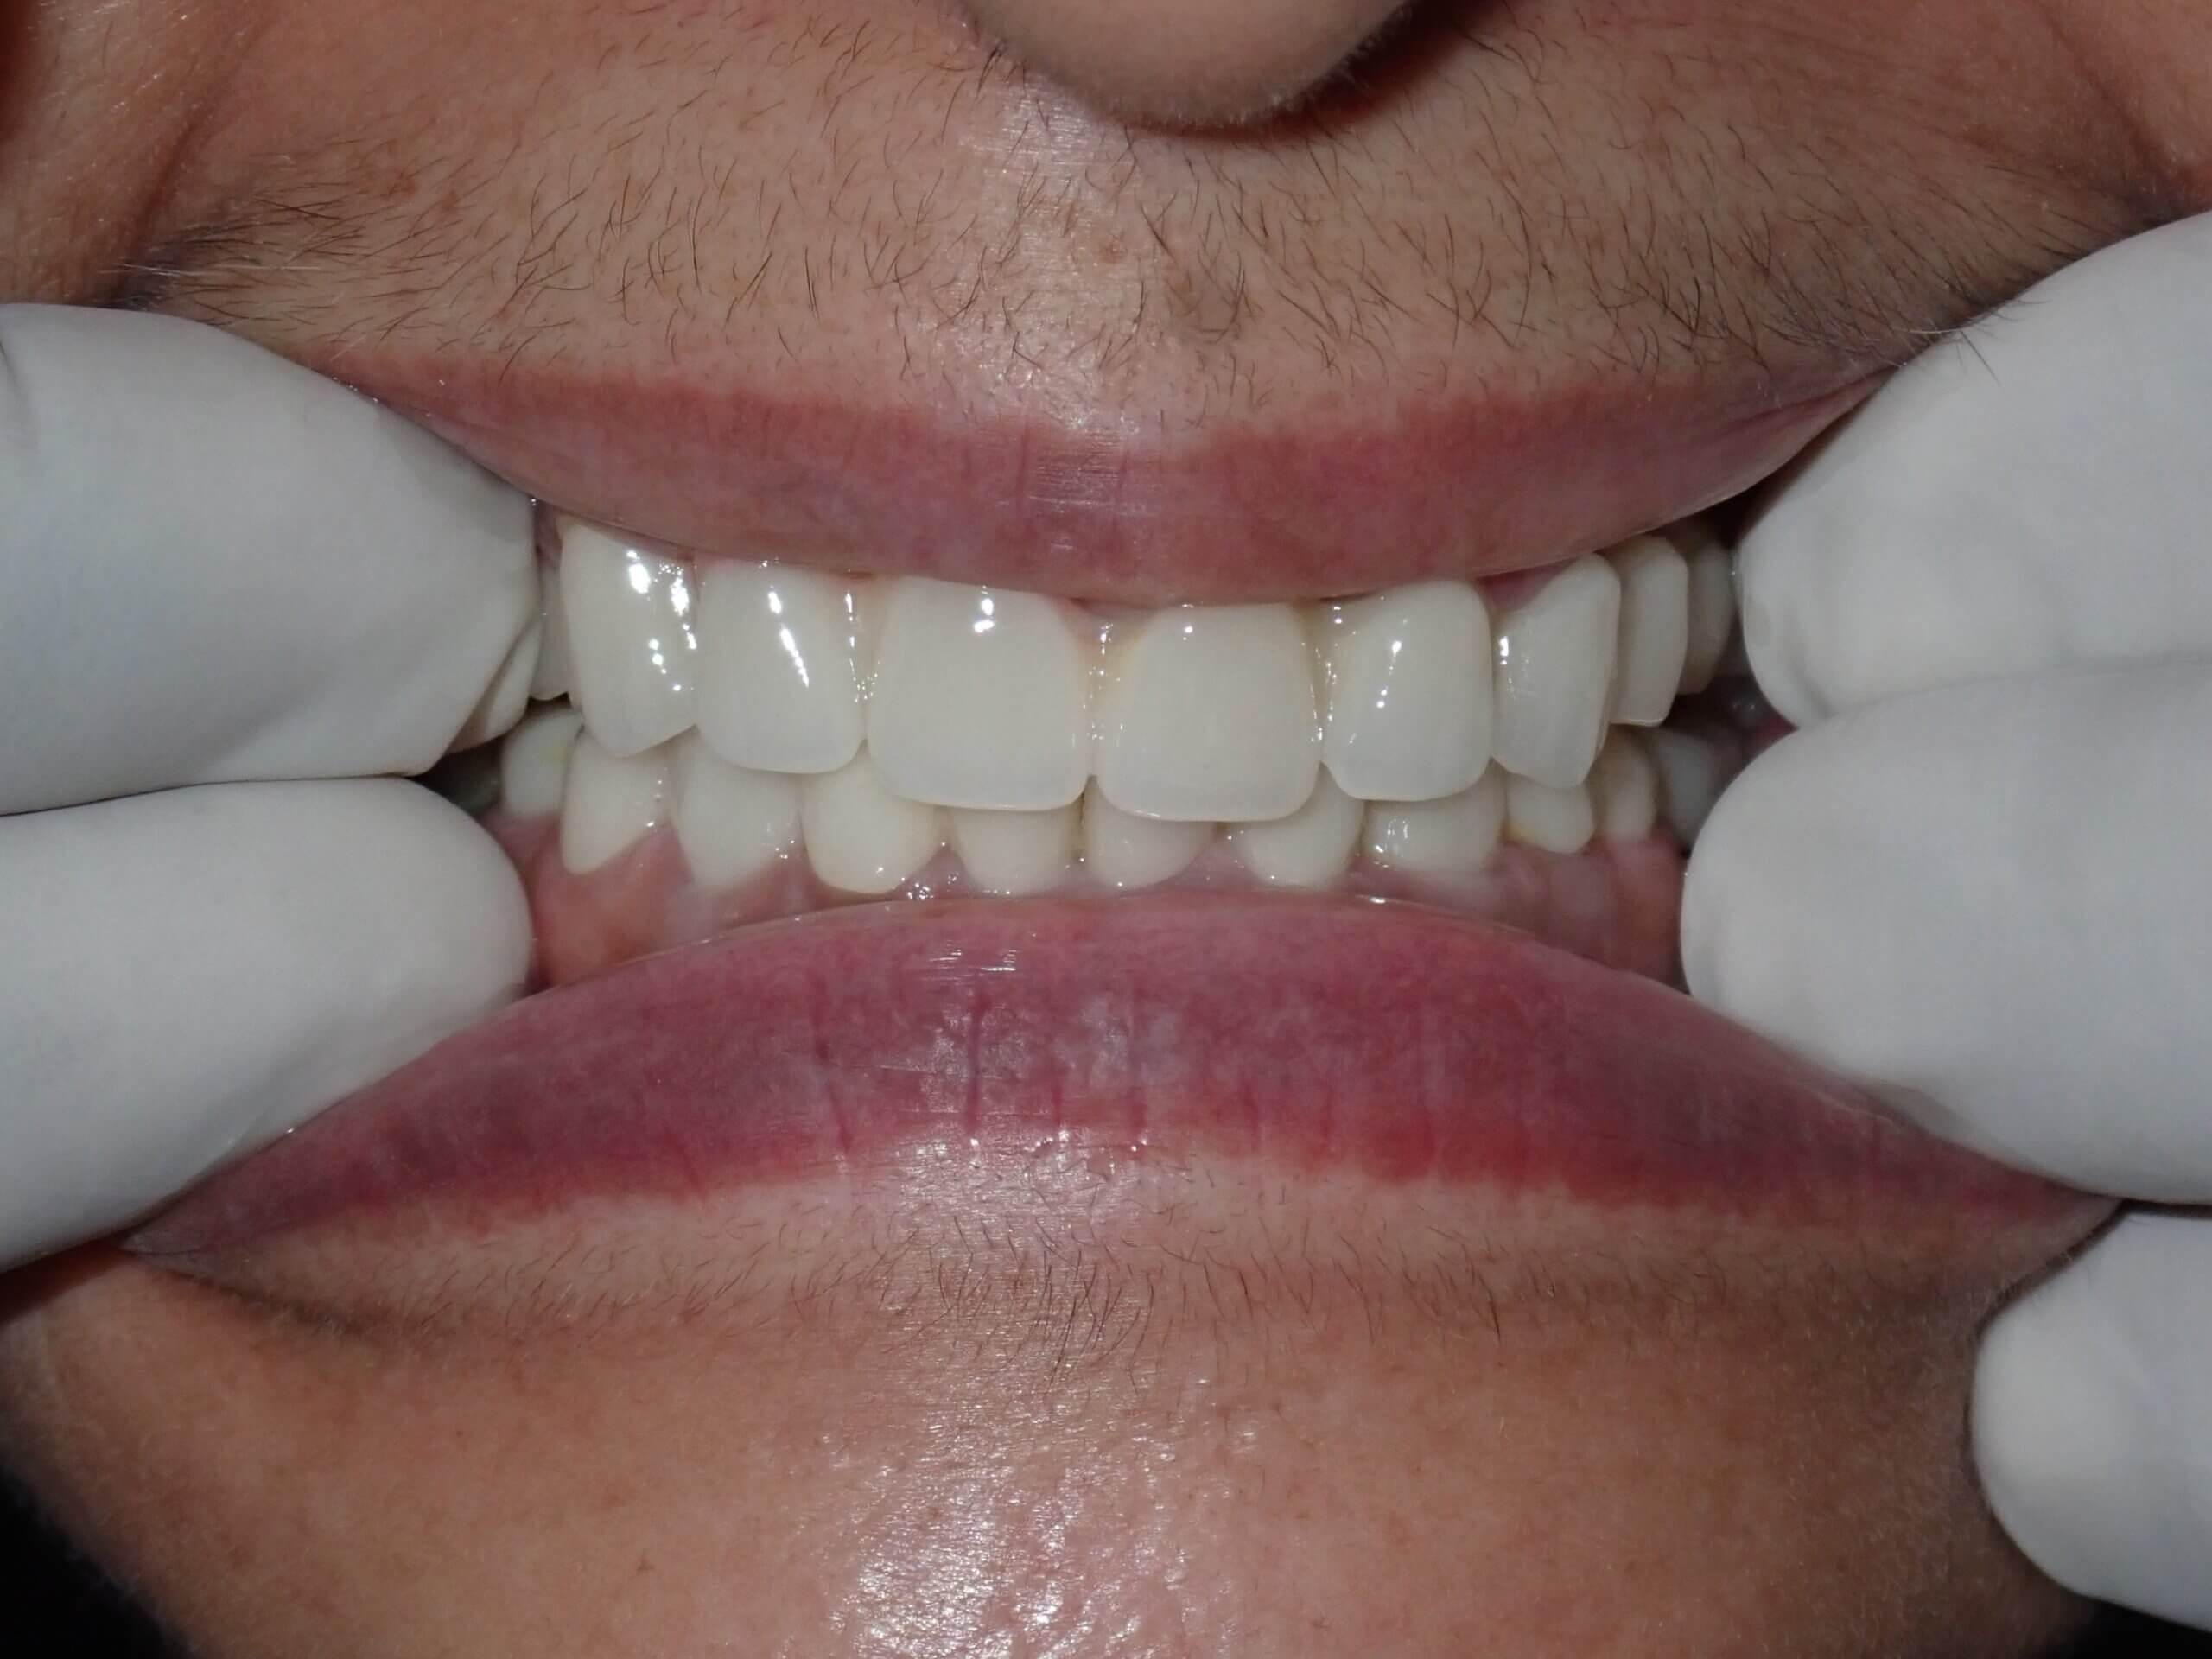

ushma Sethi India Post Treatment1 20240907

After